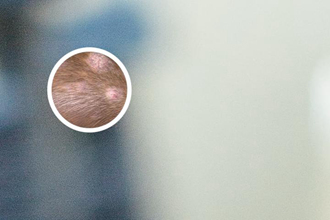

308激光,又稱準(zhǔn)分子激光,是一種科學(xué)的光療技術(shù),廣泛用于治療白癜風(fēng)。其原理是利用308nm波長(zhǎng)的激光照射白斑患處,刺激黑素細(xì)胞活性,促進(jìn)黑色素生成,從而恢復(fù)皮膚顏色。

鄭州308激光對(duì)白斑的治療的效果因個(gè)體差異而有所不同,但臨床數(shù)據(jù)顯示,有效率多達(dá)較高以上。療程通常為10次以上,每周照光1-2次,每次2-3分鐘。多數(shù)患者在一個(gè)療程后可見到顯然改善,1-3個(gè)月左右可恢復(fù)正常膚色。